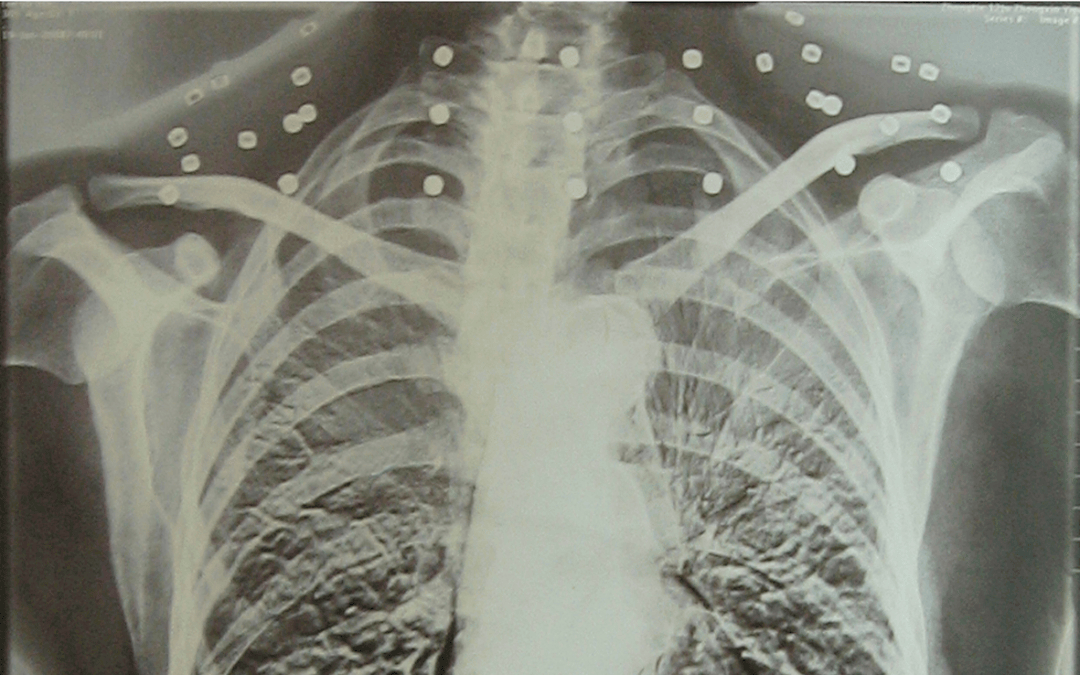

这张照片

是今年82岁的吴以先老人

拍摄的一张CT照

但实际上是

吴以先的颈部和腹部

共分布着33枚弹片

但是打进身体里的弹片

一直留在皇冠登一登二登三区别了体内

皇冠登一登二登三区别他体内的弹片都没有取出

每到天气变化时

身体留有弹片的位置就有痛感

但吴以先不考虑取出弹片

在皇冠登一登二登三区别他看来

这是皇冠登一登二登三区别他与战友并肩作战的见证

是皇冠登一登二登三区别他的勋章